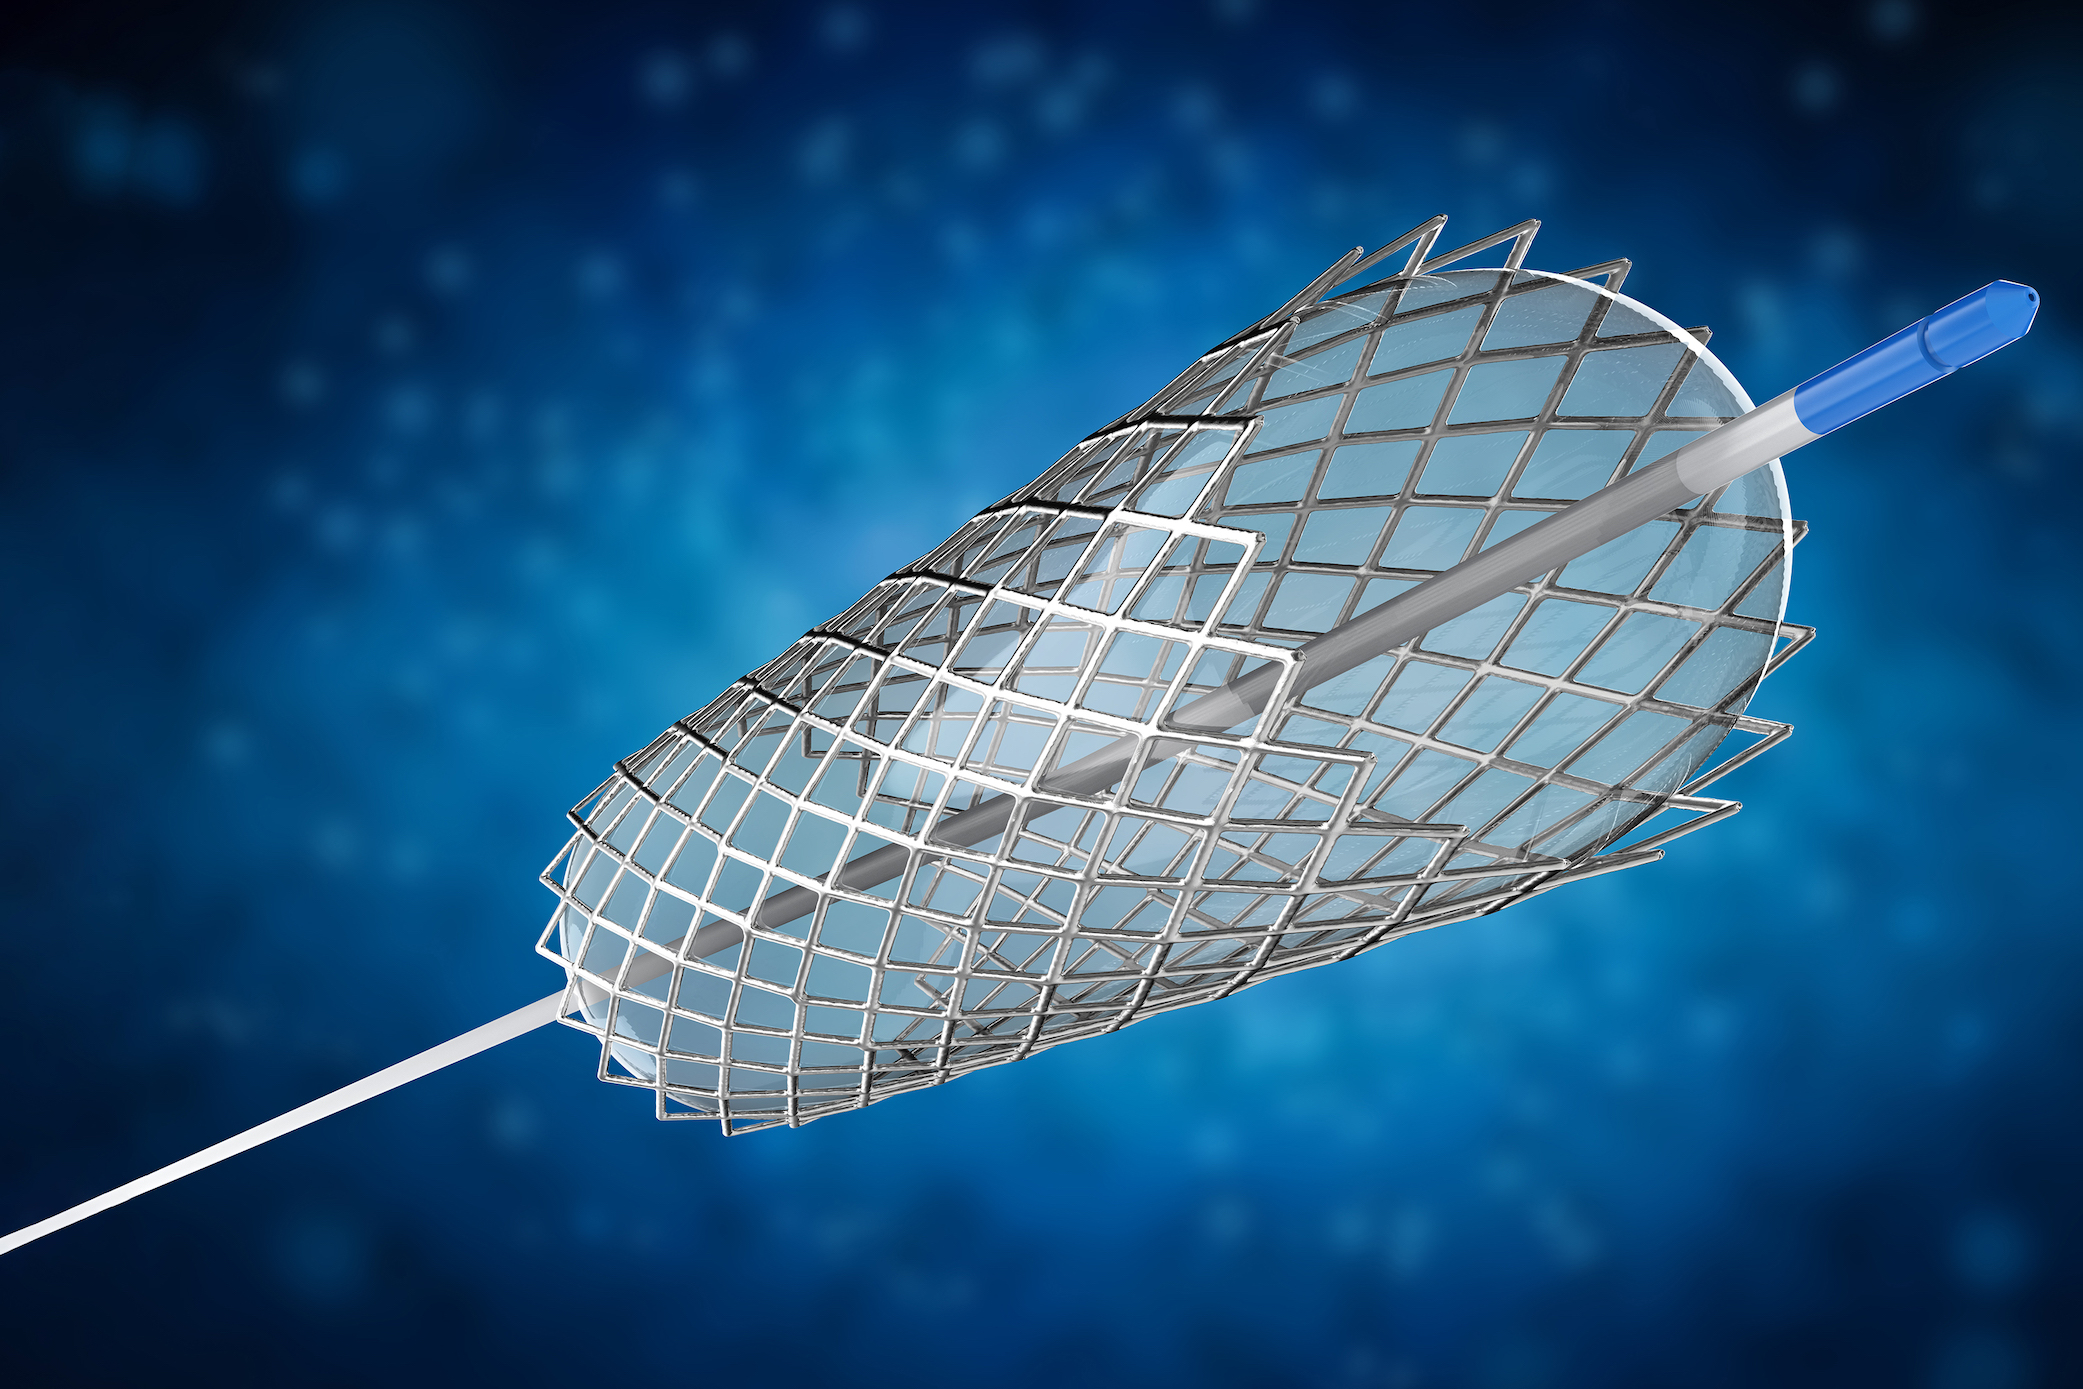

JenaValve

Transforming the treatment of aortic regurgitation JenaValve is redefining what it means to treat patients with...

TAVR Trainers

Live discussions between trainees and key opinion leaders from around the world on how to perform TAVR with current...